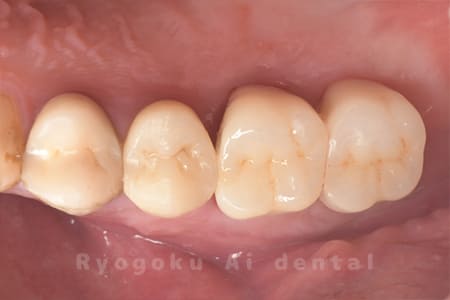

Case16

-

- 原因

- 重度カリエス

- 治療内容

- クラウンレングスニング、ジルコニアクラウン修復

- 治療費用

- 約460,000円

重度カリエスにクラウンレングスニングを施しジルコニアクラウンで修復したケースです。